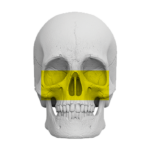

Zakres pracy tomografu.

(Badanie CBCT)

Zatoki przynosowe

( 16 cm x 17 cm )